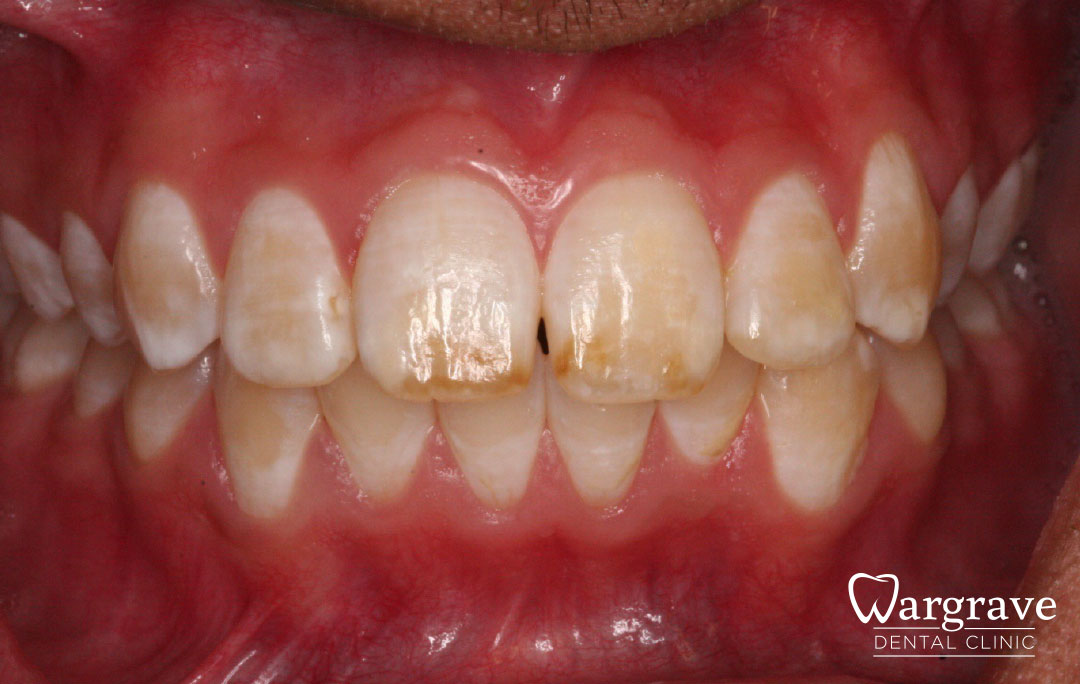

Healthy Smiles These are more advanced examples of different treatments available.All cases shown were carried out by Dr R Khurana unless otherwise stated. Immediate implants Anterior Mandible Bone Regeneration Anterior Mandibular Implant Bridge Maxillary Anterior Implant Bridge Implant stabilised ‘Life Like’ replacement dentures Implant Bridge after 10-years with zero bone loss Implant examples including ZBLC concepts Adhesive Bridge solution for a missing premolar Multidisciplinary care Orthodontics, Replacement veneers and composite bonding Adhesive Bridge solution for missing central incisors Replacement crown, Veneer and Composite Bonding Replacement Crowns and Veneer Injection Moulding using Composite Resin Equilibration Tooth Whitening to treat Developmental Discolouration